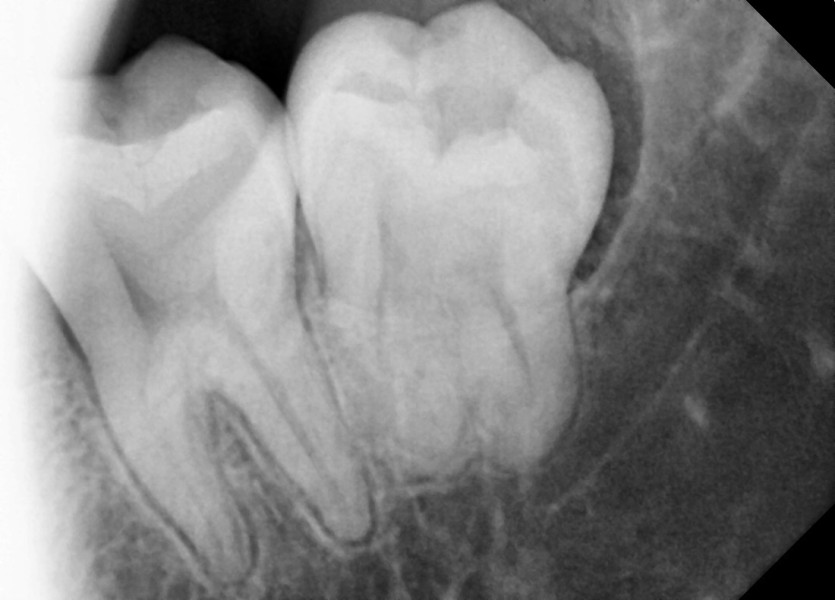

#28,38,48 사랑니 발치

구강 외과 전문의가 당일 발치했습니다.